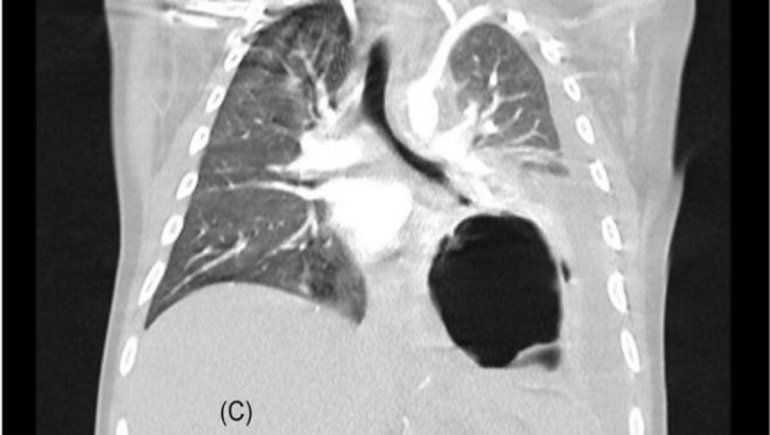

El coronavirus no es juego, nunca lo ha sido. Ahora la enfermedad se ha mostrado muy efectiva para dar vida a otras enfermedades o complicaciones dentro del organismo humano además de su afectación principal que es al sistema respiratorio. Ahora, un estudio hecho desde los Estados Unidos sostiene la posibilidad de que el coronavirus pueda ocasionar el Síndrome Inflamatorio Multisistémico (MIS-C por sus siglas en inglés) en bebés, niños y adolescentes.

El síndrome inflamatorio multisistémico es una inflamación generalizada en todo el cuerpo que puede tener otros síntomas aparte de irritación, dolor y por supuesto, hinchazón. Este síndrome suele afectar mayormente a niños y adolescentes y en casos extraños a bebés.

Lo más complicado del síndrome inflamatorio multisistémico es que en ocasiones las inflamaciones severas puede comprimir al corazón impidiéndole hacer un bombeo adecuado de sangre, desencadenando enfermedades cardíacas que pueden terminar en la muerte.